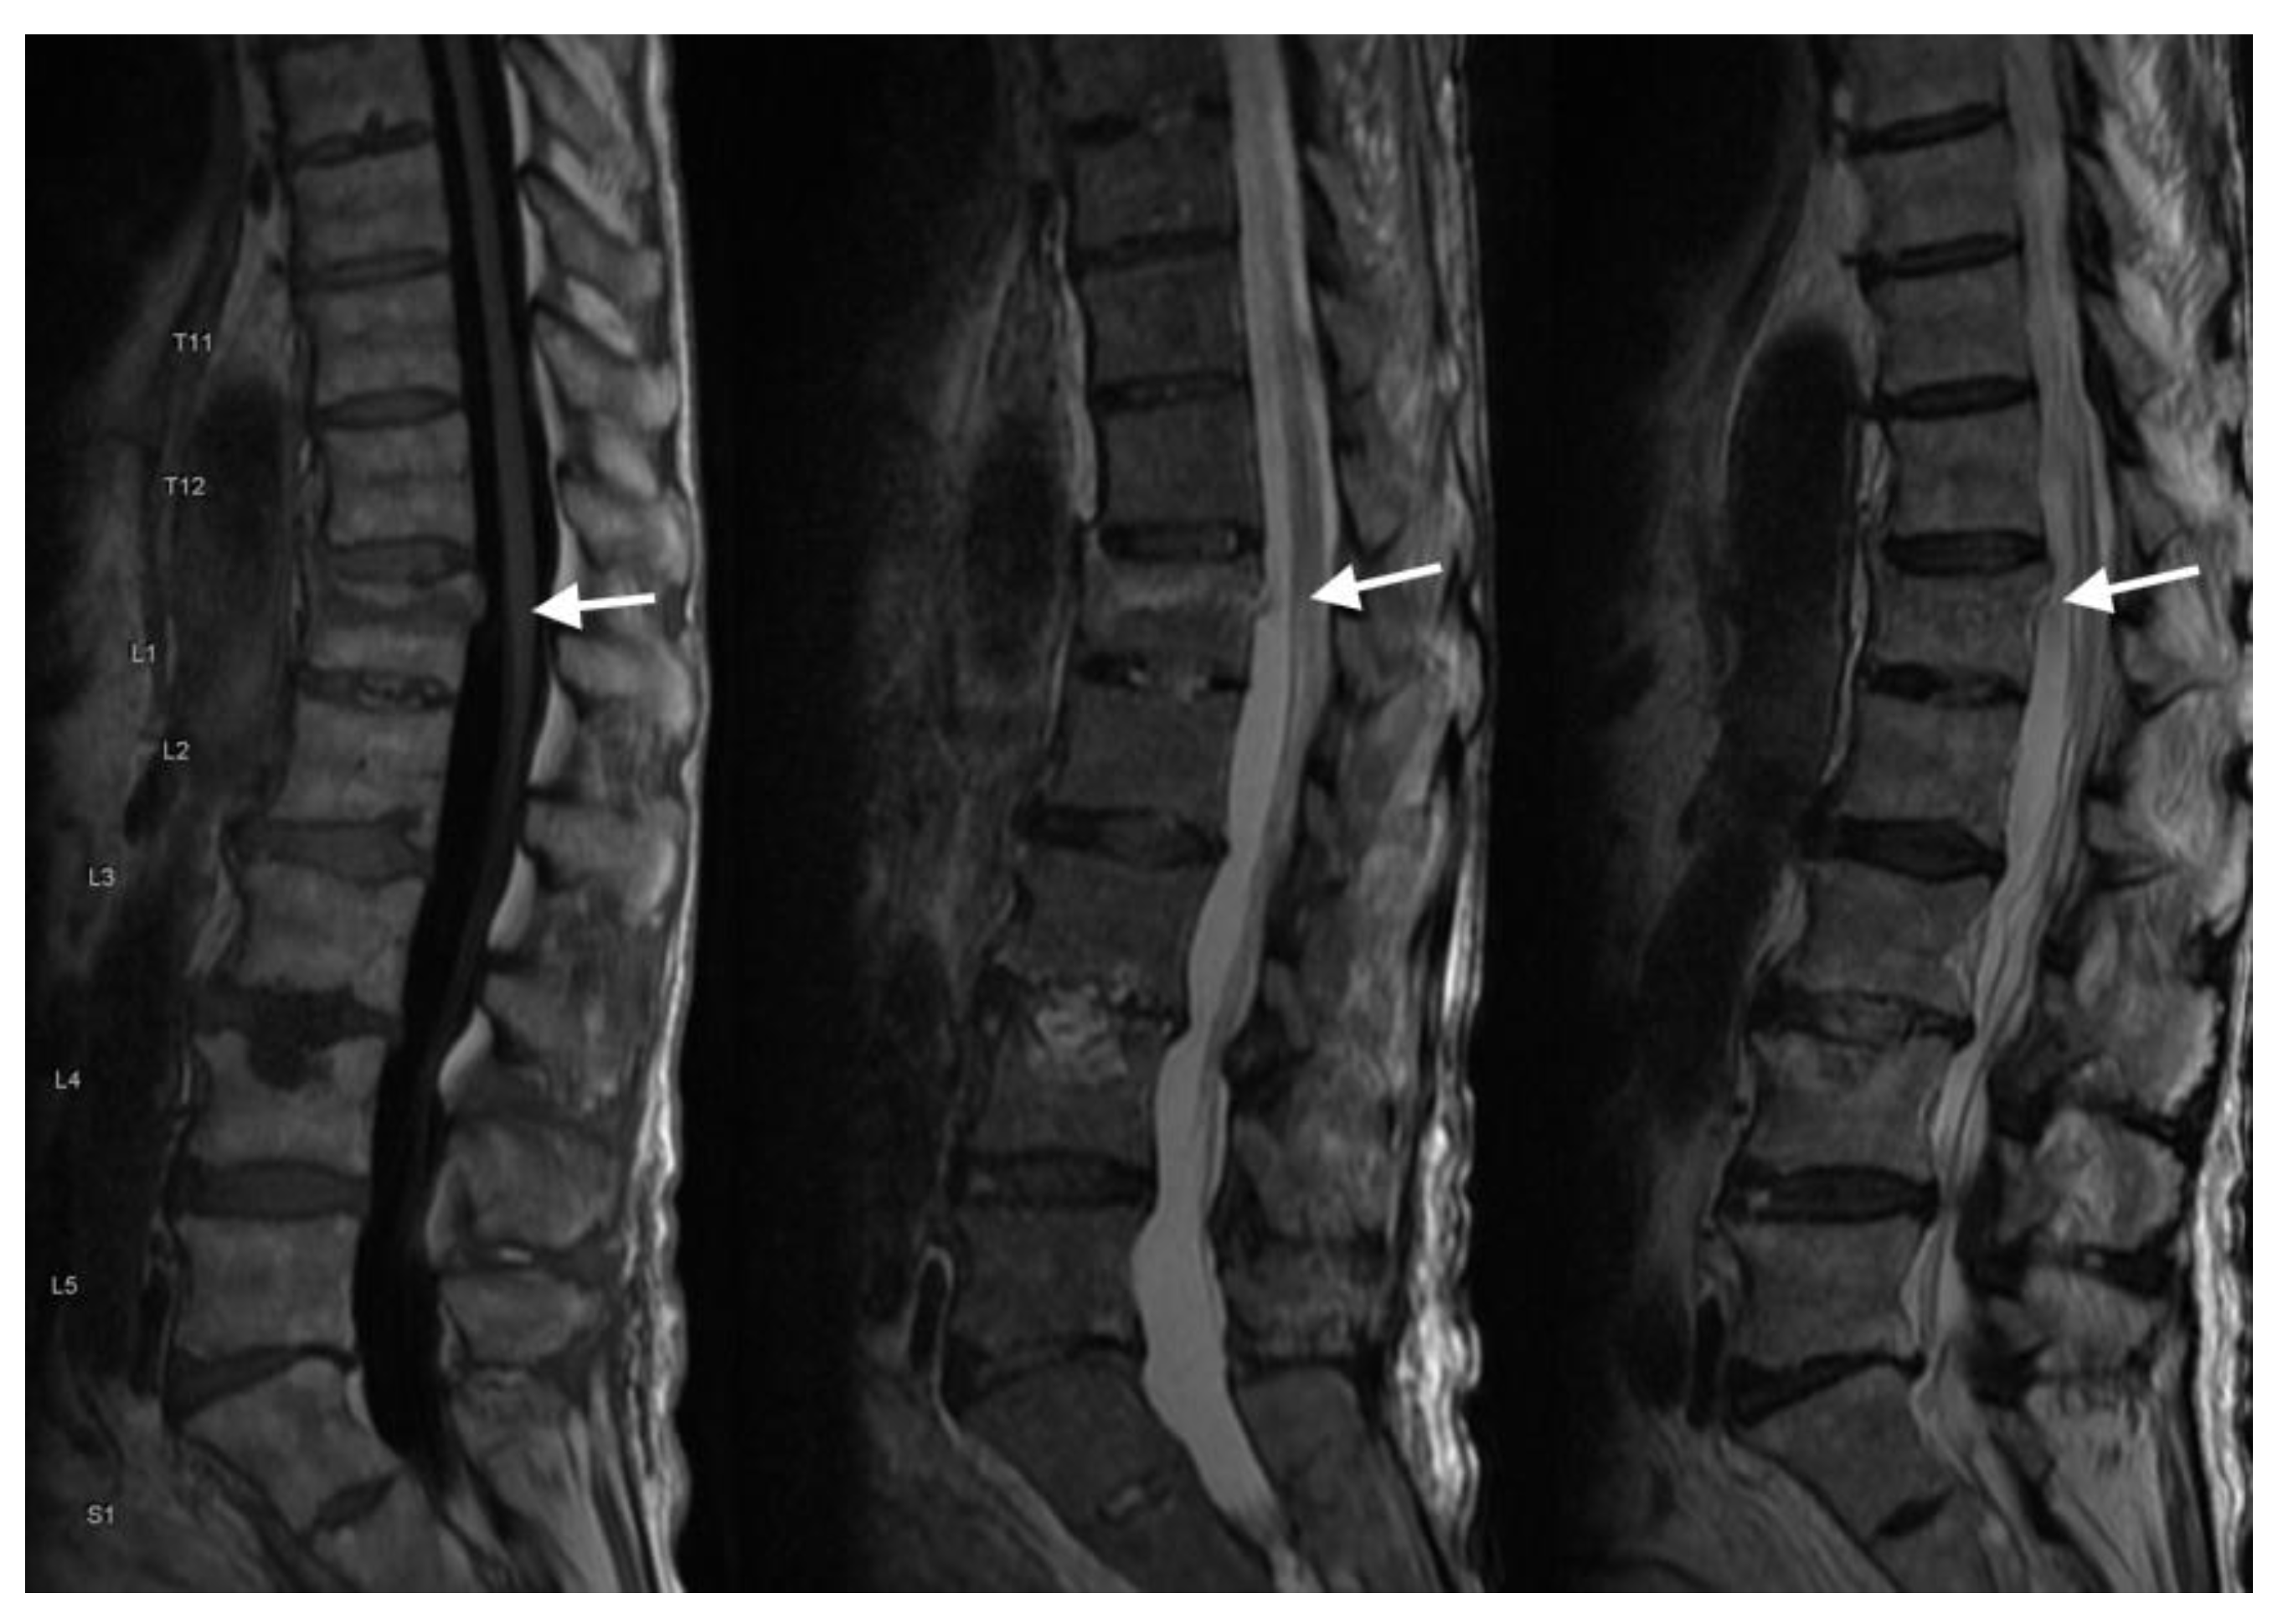

4.3. MRI Scans

| MRI | Superior soft tissue contrast, gold standard for detecting bone marrow edema |